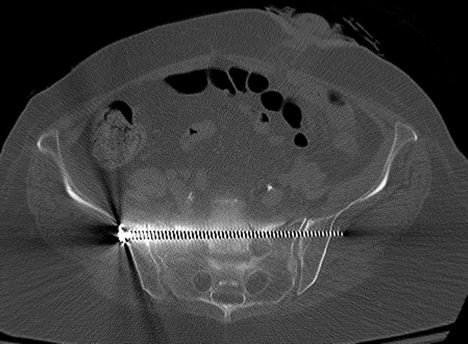

These sacral fractures are rare and occur after significant spinal axial loading. Sacral fractures are classified into three zones, zone 1, zone 2, and zone 3. A fracture involving the sacrum, a structure located at the base of the lumbar spine formed by the fusion of five sacral vertebrae. There are several classification systems for sacral fractures, but the most commonly employed are the denis classification and subclassification systems, and the isler classification system. Sacral fragility fractures cause significant pain and morbidity in the elderly population in which they occur. These sacral fractures are rare and occur after significant spinal axial loading. Possible causes, signs and symptoms, standard treatment options and means of care and support. Sacral fractures and injuries to the cauda equine. Fractures of the pelvis include sacral fractures which can vary. Login to view community videos. Plain radiographic, scintigraphic, ct, and mr imaging findings have been. Sacral insufficiency fractures in the elderly. Due to the complex nature of the injuries surgical therapeutic options are still being debated. This case was sent to me for my opinion on what to do. Sacral fractures are a common yet underdiagnosed cause of low back pain, predominantly in elderly women with osteoporosis. Ebraheim's educational animated video describes the classifications of sacral fractures. This injury is easily missed and the diagnosis is often delayed as it is difficult to detect on the anteroposterior view of the pelvic radiograph.